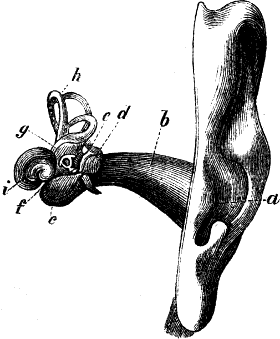

Diese Zusammendrückung der Luft empfindet der Taucher an dem

unangenehmen Druck auf die Athmungsorgane, die Blutgefäße

und das Trommelfell im Ohre.